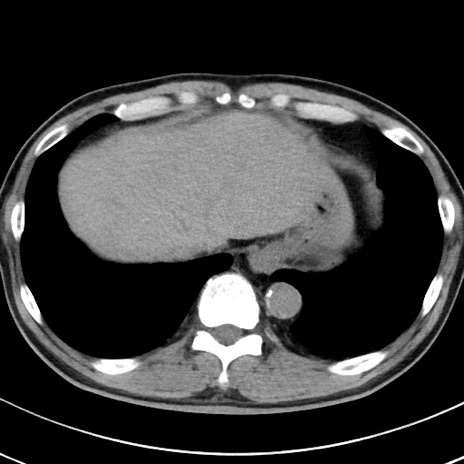

【腹部TIPS】症例29 参考症例 CT(横断像)

症例

70歳代男性